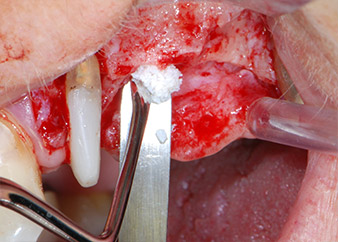

Nous avons toutefois maintenu notre projet initial de conservation des deux dents comme piliers temporaires d'un bridge pendant la période de six mois nécessaire à l'ostéointégration des implants. À la prochaine incision, la situation devrait être réétudiée. Premièrement, afin de gérer le problème endoparodontal, la surface de racine restante a été soigneusement débridée à l'aide d'un équipement piézoélectrique (Piezomed, W&H, utilisé avec l'insert en forme de spatule S1, initialement conçu pour limer la paroi sinusienne latérale) (Fig. 4).

débridement parodontal

Fig. 4 : Pour préserver la dent comme pilier temporaire, un débridement parodontal a été pratiqué à l'aide d'un équipement piézoélectrique...